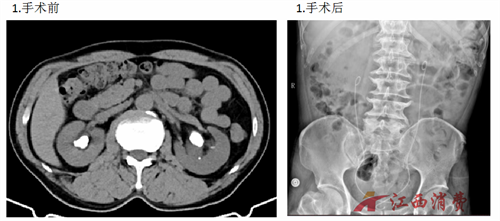

2026年新年伊始,上饶市立医院泌尿外科团队传来捷报——连续成功为三例双侧肾输尿管结石患者实施输尿管软镜钬激光碎石术,所有病例均实现一次性完整粉碎结石,即刻清石率达到极高水平,患者术后恢复顺利,彰显了上饶市立医院在复杂泌尿系结石微创诊疗领域的过硬实力。